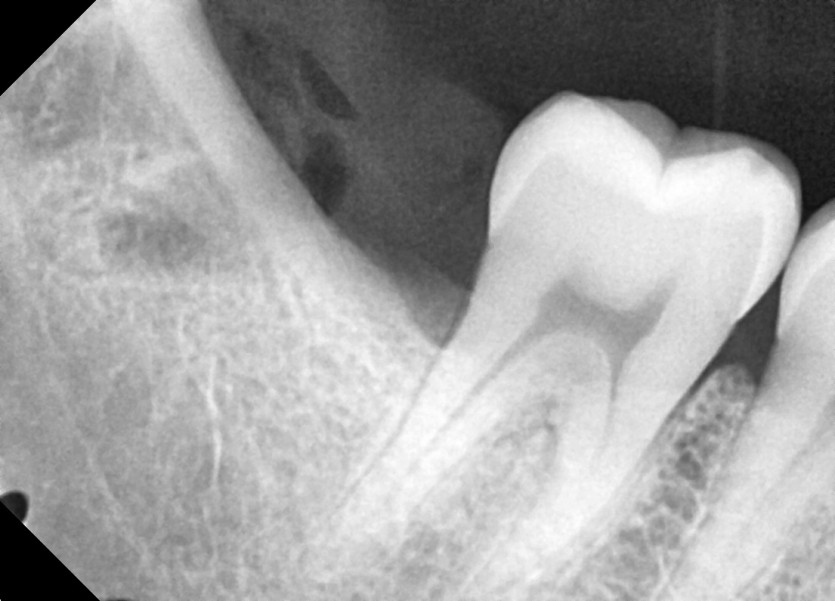

#18,48 사랑니 발치

구강 외과 전문의가 당일 발치했습니다.